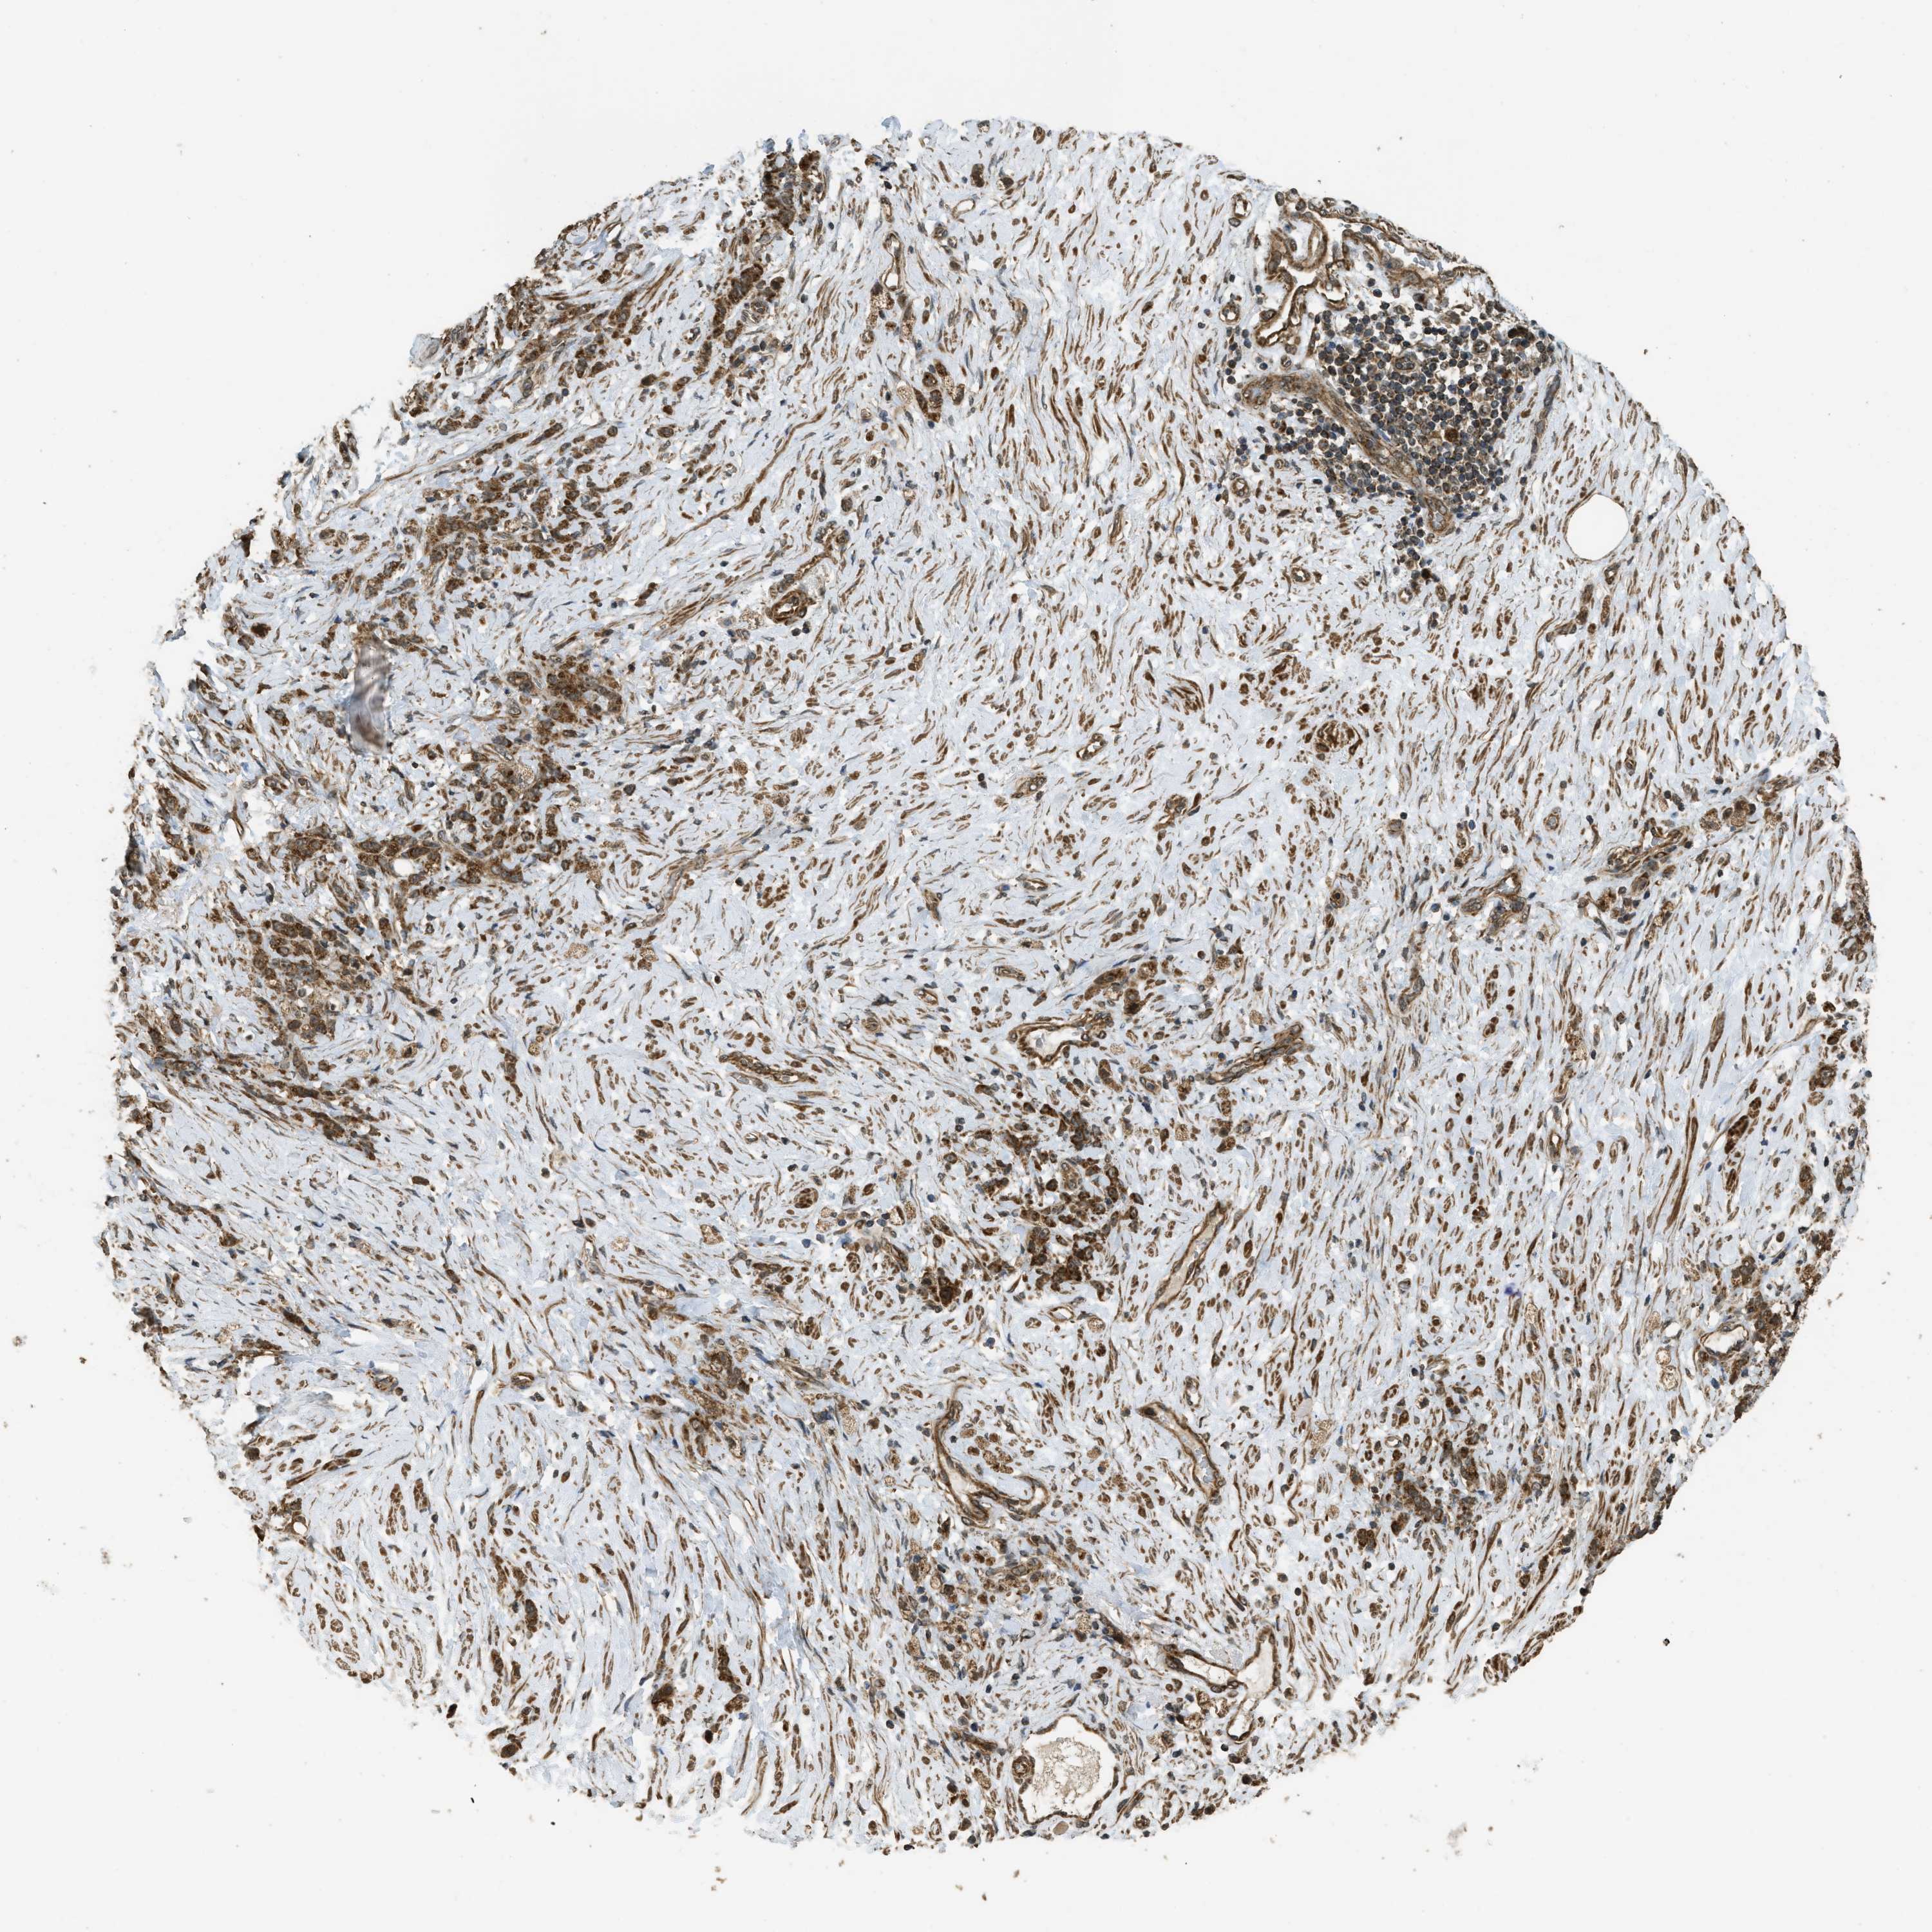

STOMACH CANCER - Protein expressioni

A mouse-over function shows sample information and annotation data. Click on an image to view it in a full screen mode. Samples can be filtered based on level of antibody staining by selecting one or several of the following categories: high, medium, low and not detected. The assay and annotation is described here.

Note that samples used for immunohistochemistry by the Human Protein Atlas do not correspond to samples in the TCGA dataset.

Antibody stainingi

Antibody staining in the annotated cell types in the current human tissue is reported as not detected, low, medium, or high, based on conventional immunohistochemistry profiling in selected tissues. This score is based on the combination of the staining intensity and fraction of stained cells.

Each image is clickable and will lead to virtual microscopy that enables deeper exploration of all samples and also displays staining intensity scores, fraction scores and subcellular localization as well as patient and tissue information for each sample.

Antibody HPA051322

Antibody CAB017111

Staining

High

Medium

Low

Not detected

Intensity

Strong

Moderate

Weak

Negative

Quantity

>75%

75%-25%

<25%

None

Location

Nuclear

Cytoplasmic/membranous

Cytoplasmic/membranous,nuclear

Adenocarcinoma, NOS

Adenocarcinoma, High grade